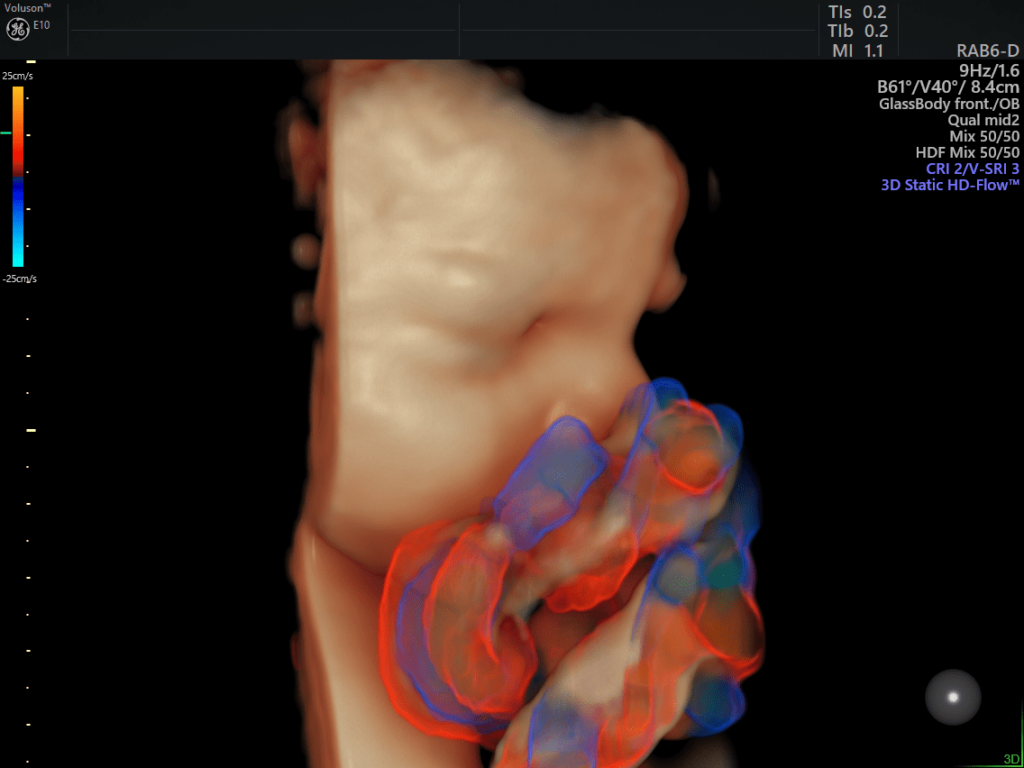

HDlive™ Flow e HDlive™ Flow Silhouette: Applica tutte le caratteristiche presenti in HDlive™ e HDlive™ Silhouette al rendering con campionamento di flusso volumetrico Color Doppler, Power e HDFlow™.